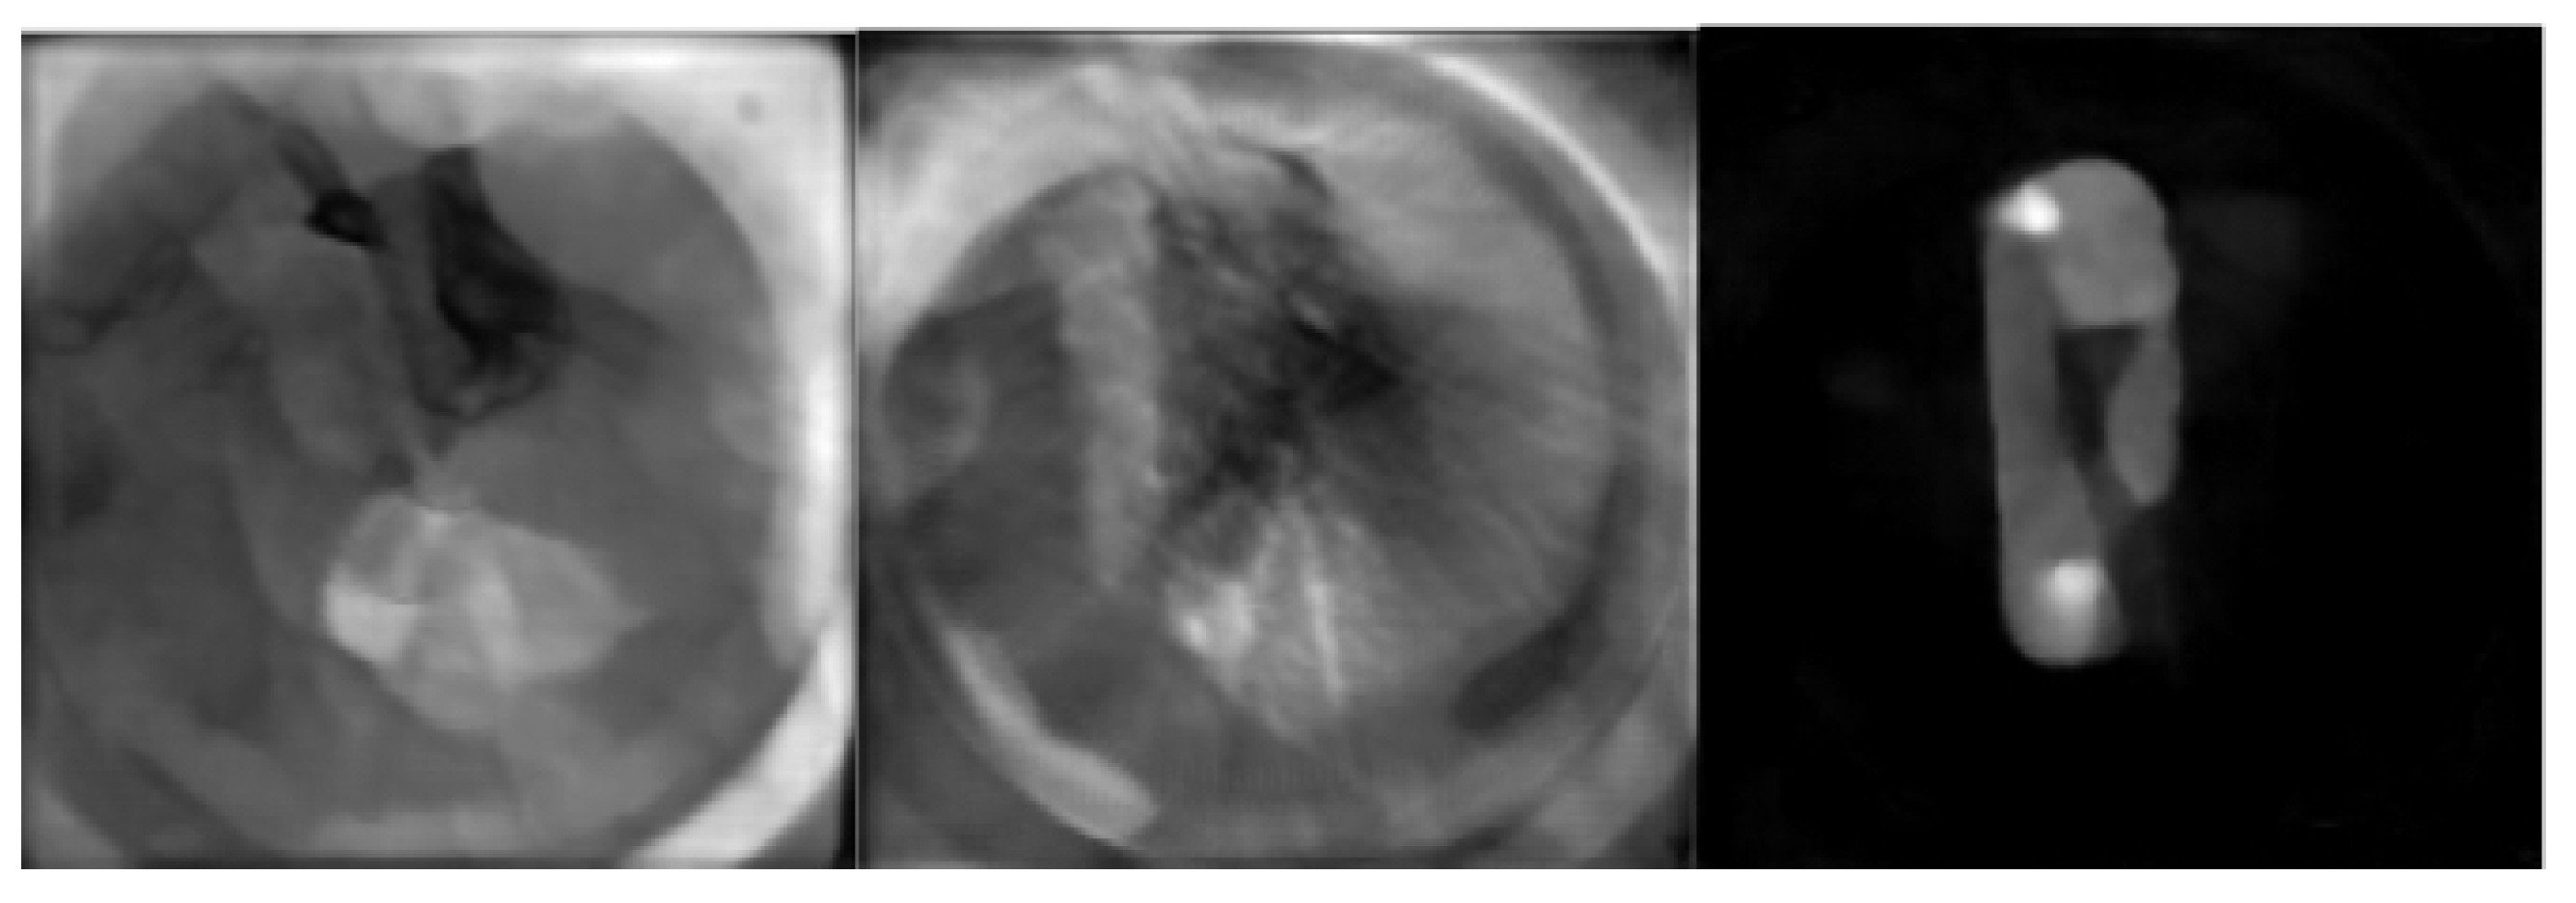

3.2. Results on miniPET-3 Data